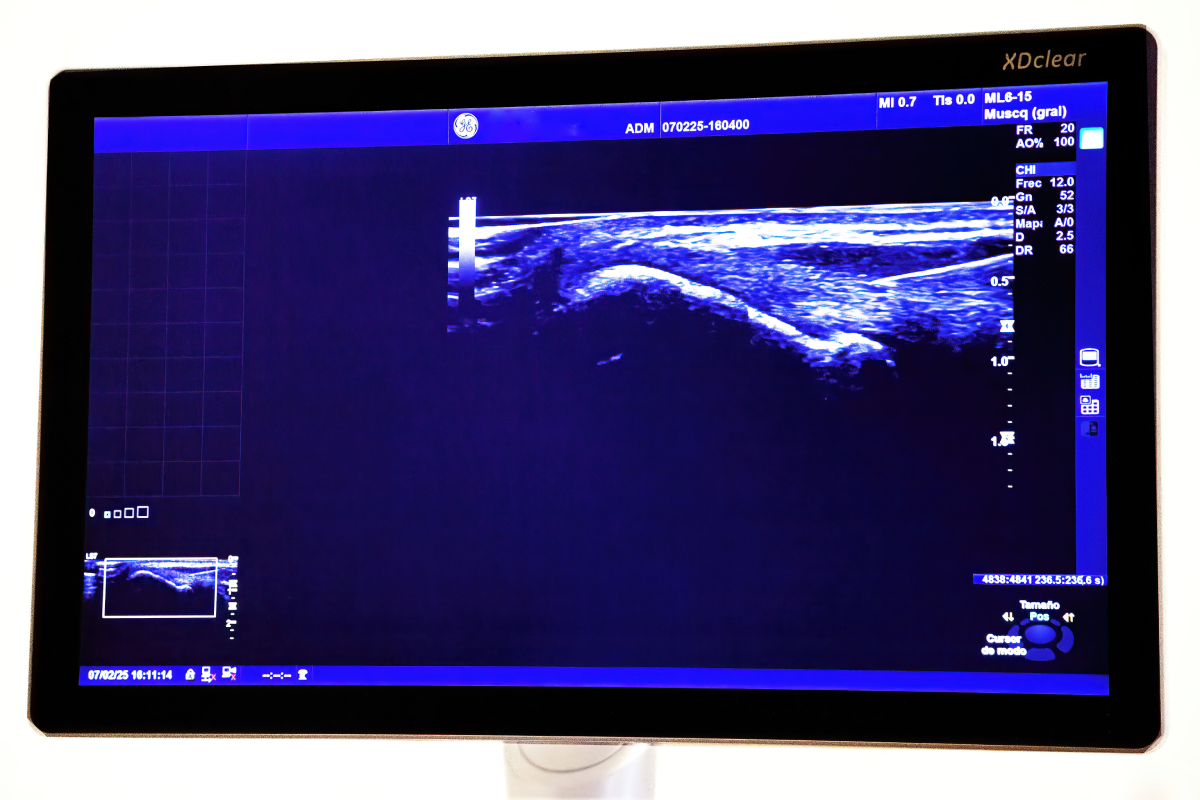

Será muy importante poder realizar un examen ecográfico para poder tener una imagen de las diferentes estructuras que podrían estar dañadas del sistema músculo-esquelético, tendones, ligamentos y articulaciones y valorar alcance de esta lesión.

A través de la ecografía podremos establecer un diagnóstico tanto en estático como en dinámico.

Como venimos explicando, la posibilidad de hacer una valoración con ecografía nos dará una imagen en ese preciso momento de la lesión que tenemos delante pudiendo hacer una valoración más precisa y objetiva.